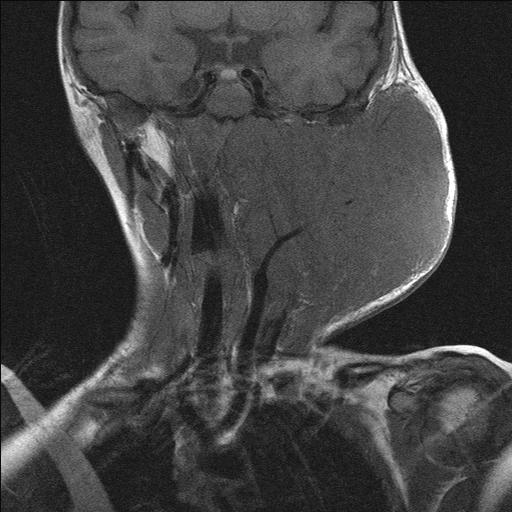

There are two main types of rhabdomyosarcoma, plus some rare variants. Embryonal rhabdomyosarcoma mainly affects young children but is the most common type at all ages. This variant is called ‘embryonal’ because of the characteristic appearance of the malignant cells, which resemble the developing muscle cells of a 6 to 8 week old embryo. The second main type, alveolar rhabdomyosarcoma occurs at all ages equally and accounts for approximately 20 to 30 % of rhabdomyosarcoma cases. It affects most commonly the head and neck region but also the extremities (see Figure 2). There does not seem to be a genetic predisposition for alveolar rhabdomyosarcoma.

Figure 2: MRI of alveolar rhabdomyosarcoma in a 4 year old child.